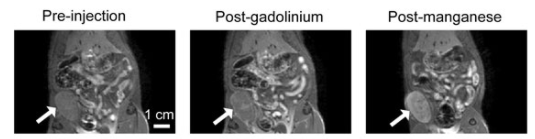

MRI technique enables long-term tracking of transplanted stem cell–derived heart cells. February 27, 2026.